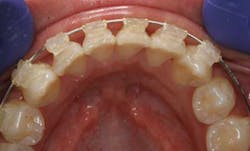

Let me clarify what Cfast is. Cfast allows us to provide limited orthodontic treatment that focuses on making the teeth the patients see (typically cuspid-to-cuspid) straighter. Because these teeth have single roots and the bone is not as dense, the treatment goes quickly so we can make this much more affordable relative to what many patients think about when considering traditional, comprehensive orthodontics. The dental laboratory determines actual placement of the brackets on the stone models, making this very exact. Placement is guided by a tray delivery system.

With Cfast, we use ceramic brackets and tooth-colored nickel-titanium wires, so it is very esthetic. An advantage I have enjoyed over the clear tray systems is patient compliance, which is automatic since all the “hardware” is bonded into place. Treatment times are shortened to typically four to seven months. This photo actually shows the author in Cfast: